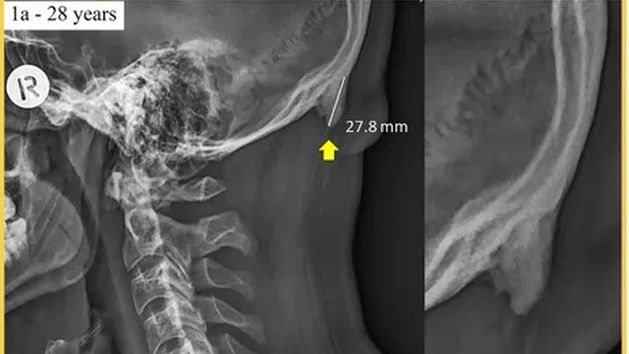

Naukowcy wskazują, że w grupie osób pomiędzy 18 a 30 lat u 40 proc. badanych wykryto specyficzną narośl kostną zlokalizowaną w tylnej części czaszki, która nie występuje u większości ludzkiej populacji.

Według badań nowy wyrostek kostny może mieć długość ok. 3 cm, a powodem jego pojawienia się jest nagminne nachylenie kręgosłupa szyjnego związane z korzystaniem ze smartfonów.

Badacze twierdzą, że organizm wykształca nową narośl aby zrównoważyć „wirtualny” ciężar, który może sięgać nawet 27 kilogramów.